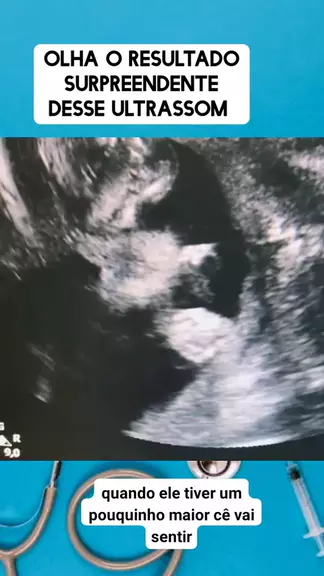

olha o resultado da ultrassom #medico #medicina #Saúde #viraliza